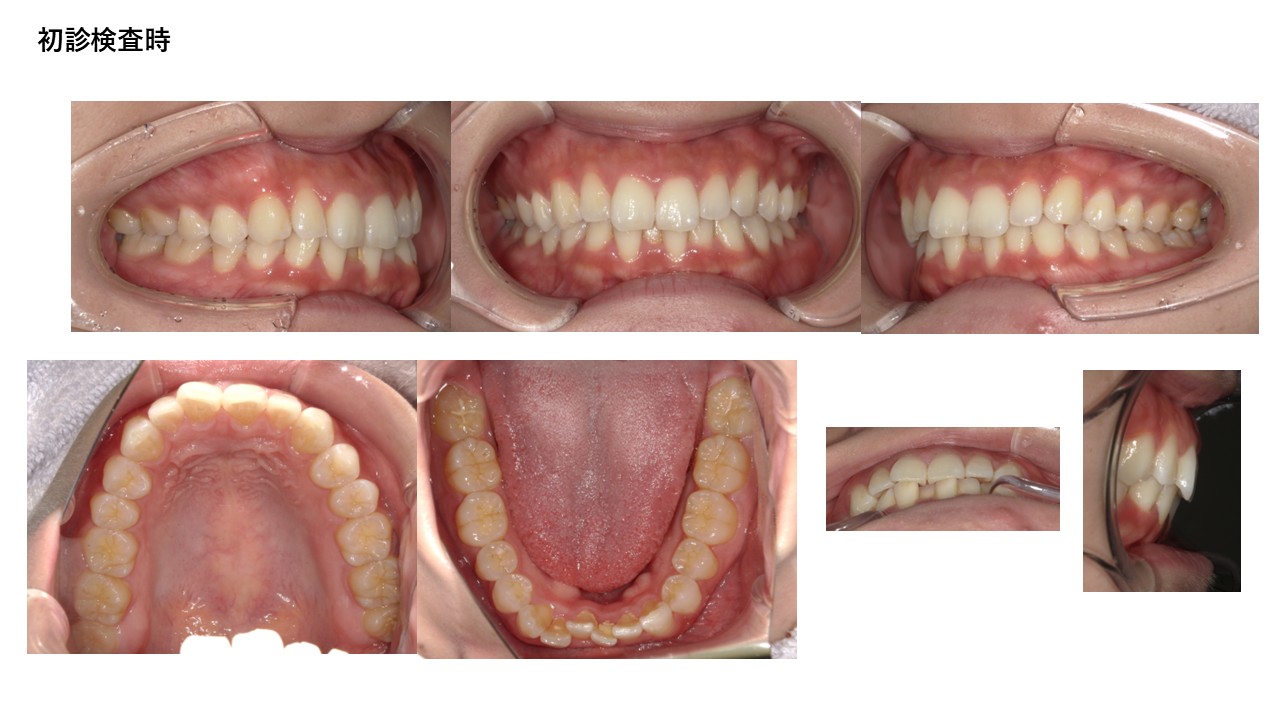

裏側ワイヤー矯正

| 主訴 | 叢生、前突 |

|---|---|

| 年齢 | 30代 |

| 治療期間 | 1年(継続中) |

| 治療回数 | 12回 |

| 治療に用いた主な装置 | カスタムメイド型リンガルブラケットデジタル矯正装置(WIN) |

| 治療費 | 1,300,000円(税別) |

| リスク・副作用 |

1. 矯正装置を装着すると、不快感や痛みが生じることがあります。通常、数日〜1週間ほどで痛みが消失し、慣れることが多いです。 2. 歯の動き方には個人差があり、予想された治療期間より長引く可能性があります。 |